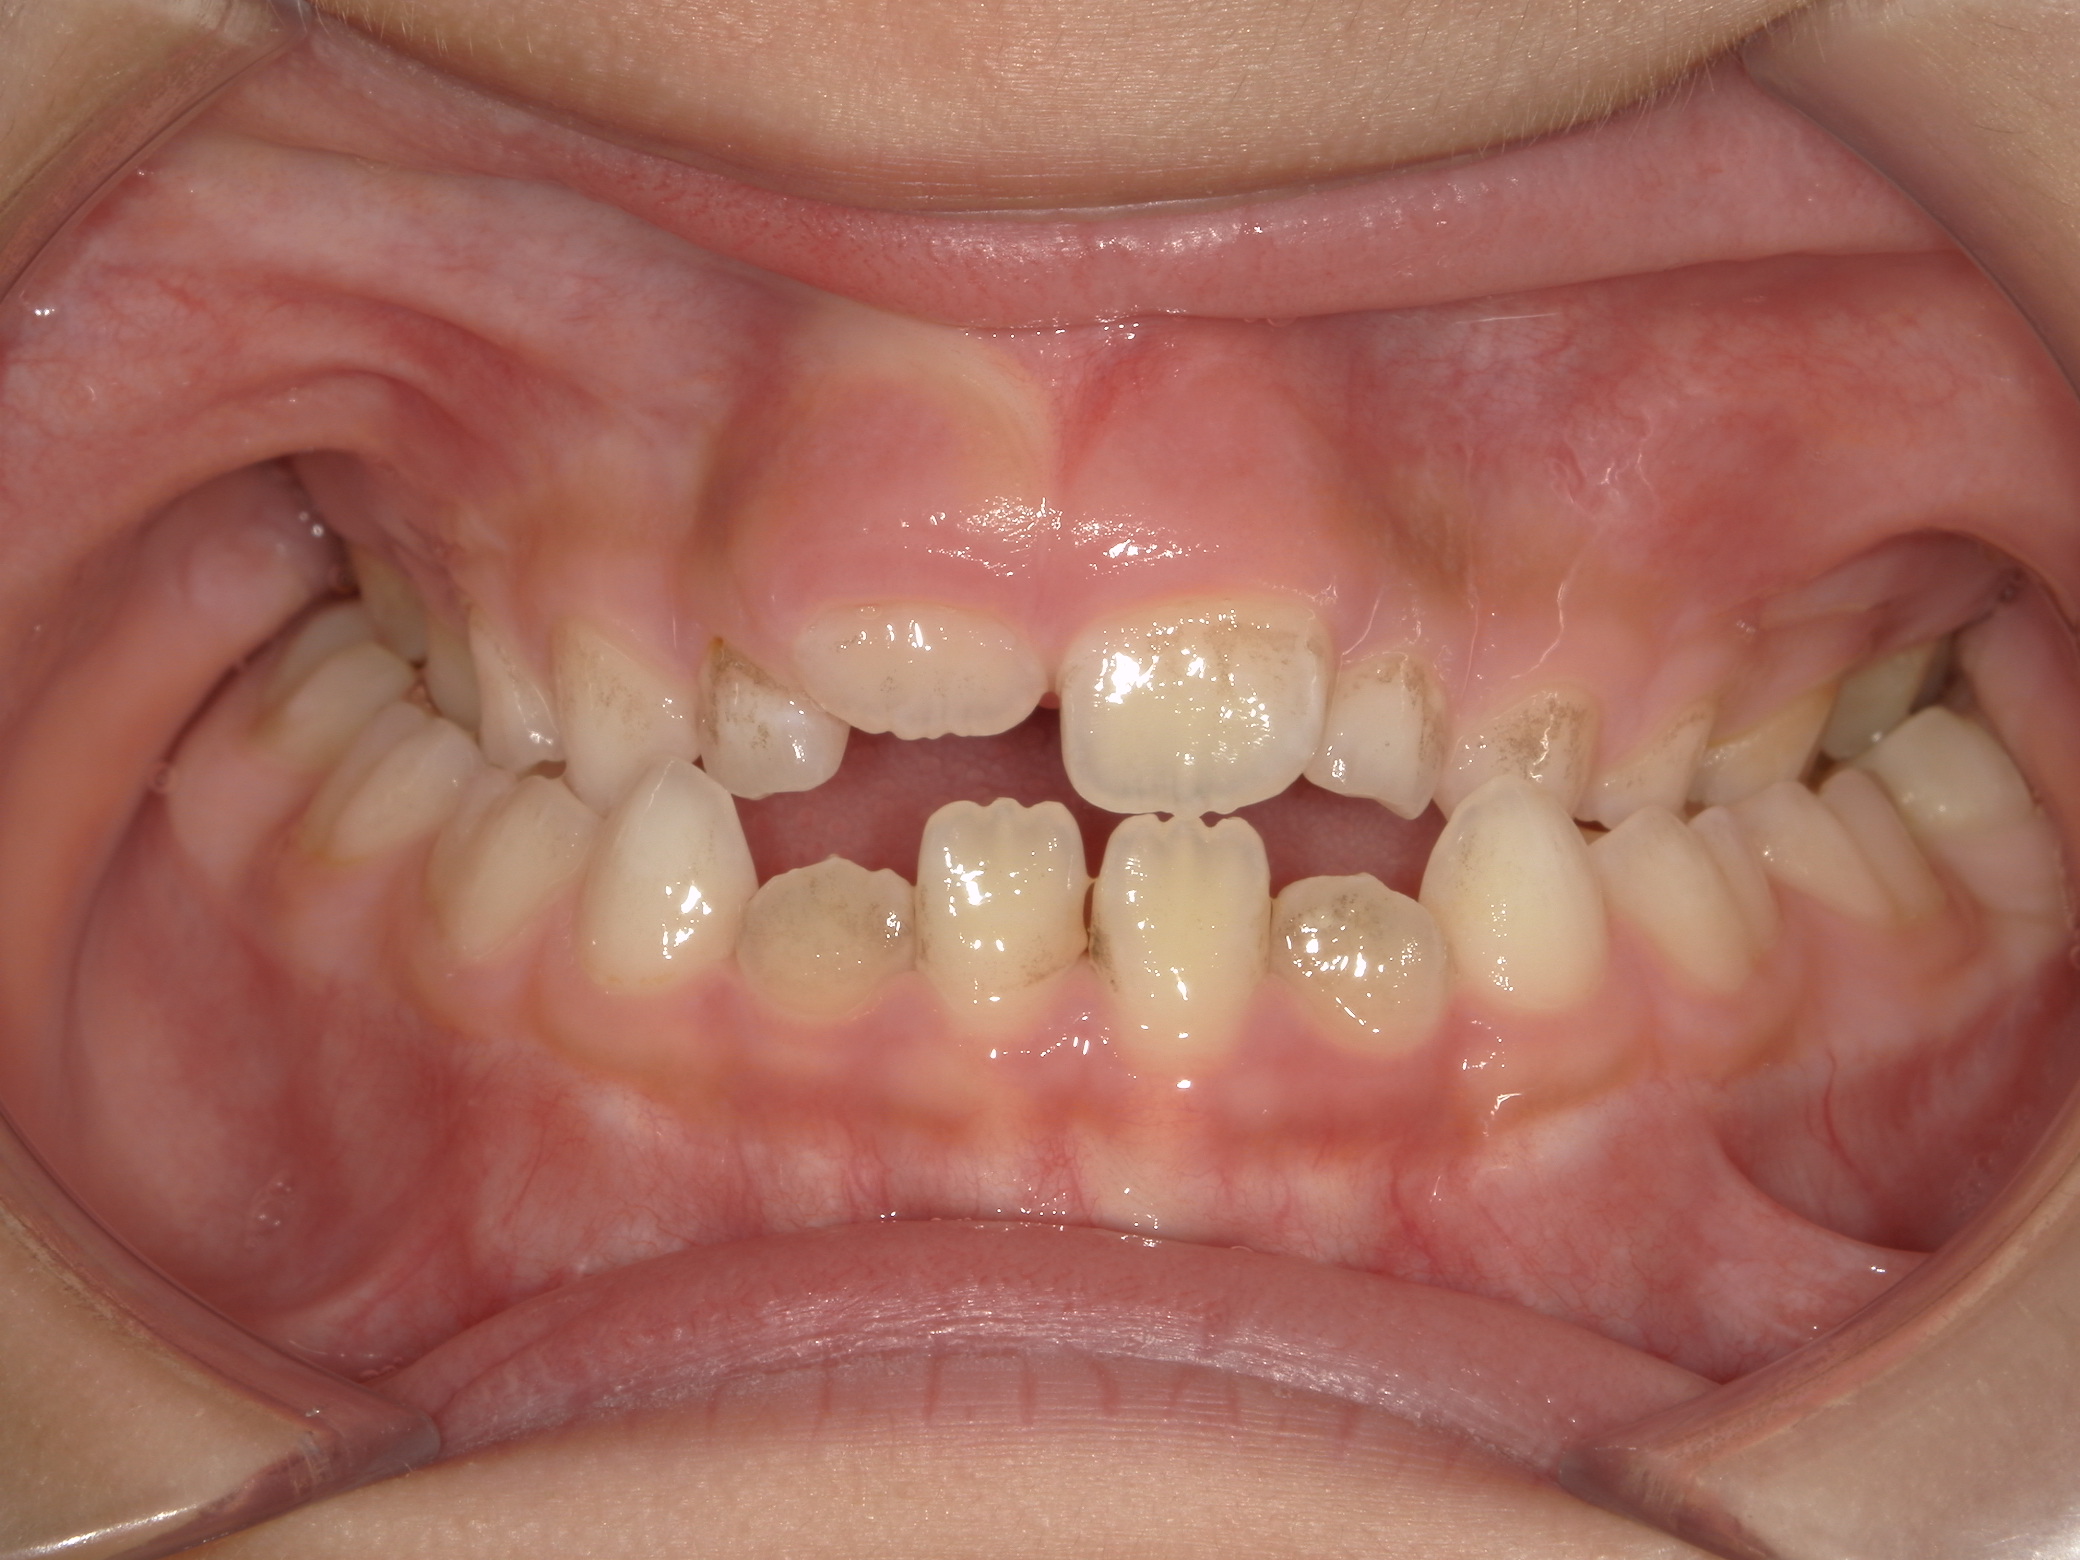

歯の位置異常(犬歯位置異常)

8歳 男性

歯列弓拡大、前歯の正常被蓋獲得、犬歯の誘導

拡大床、部分ワイヤー

495,000円(税込)

2年6か月

左上犬歯の位置異常が初診時検査で認められました。外科的誘導は行っておらず、歯列弓をしっかり拡大し、乳歯を意図的に抜歯してあげることで本来の位置へ誘導することに成功しています。矯正歯科医院での適切な判断で外科処置を回避できた症例です。

2期治療にて仕上げの矯正治療を行う予定です。